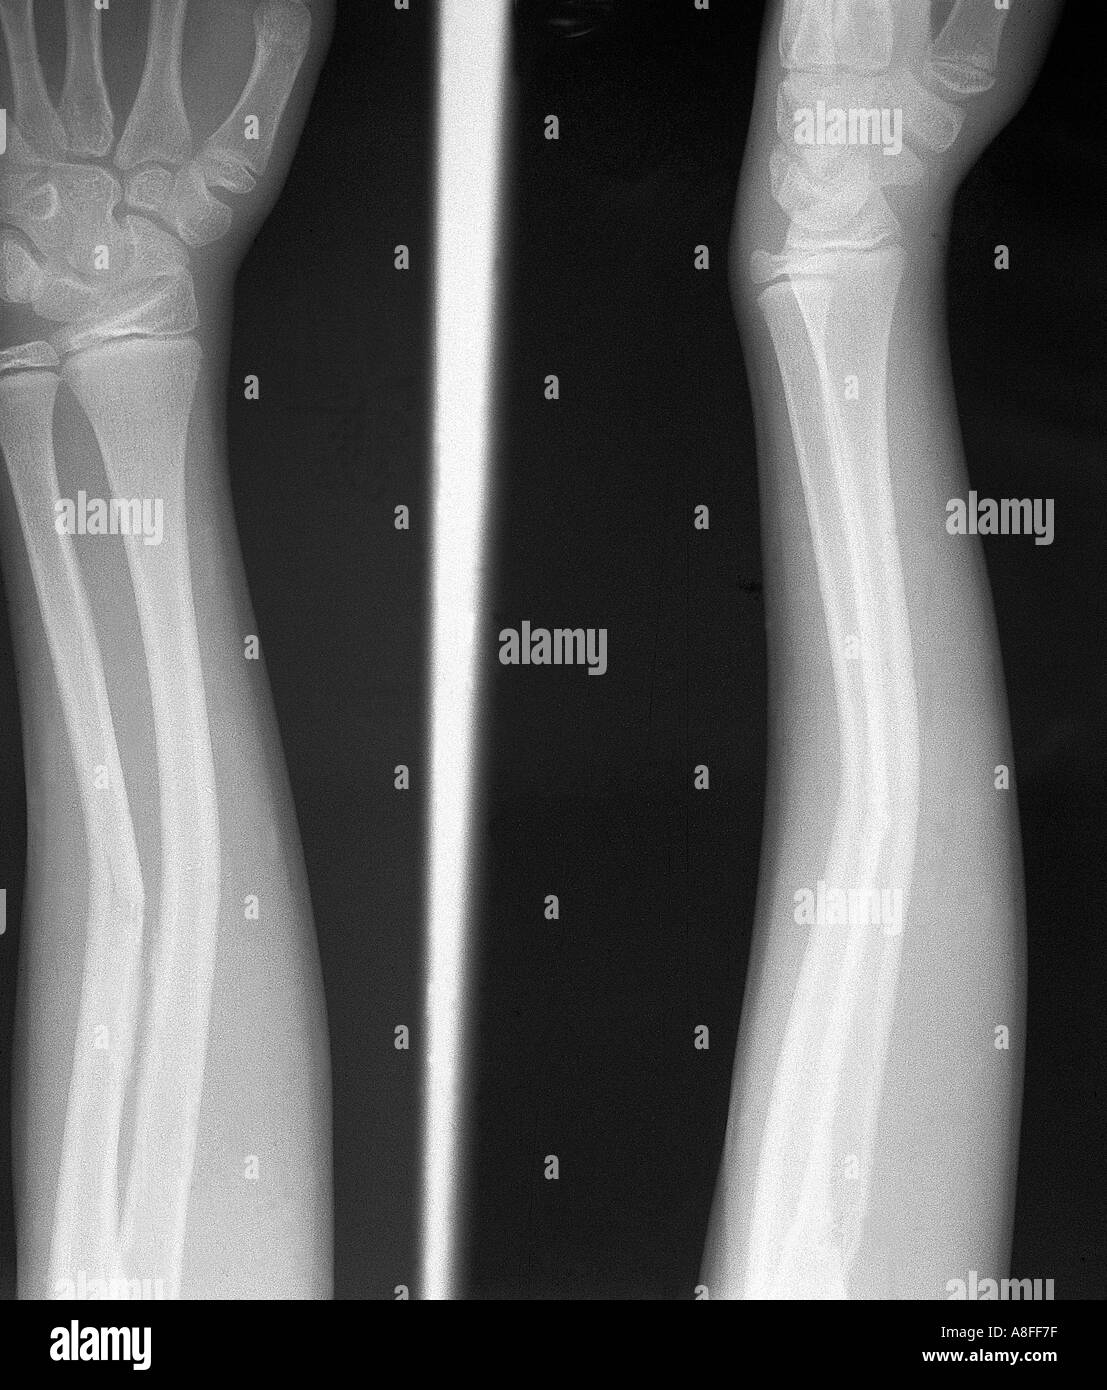

From www.alamy.com

forearm xray of a 3 year old girl showing a buckle, greenstick Stock Greenstick Fracture X-Ray They may also use magnetic. Due to skeletal immaturity, they may present as greenstick fractures. The rest of the bones on both sides are intact. Greenstick fractures usually affect the forearm and upper arm bones, and are often caused by falling on an outstretched arm. A greenstick injury comprises a. Children have more pliable bones than adults and are therefore. Greenstick Fracture X-Ray.

X ray greenstick fracture of forearm Stock Photo 2835048 Alamy Greenstick Fracture X-Ray Due to skeletal immaturity, they may present as greenstick fractures. They may also use magnetic. A greenstick injury comprises a. The rest of the bones on both sides are intact. Greenstick fractures usually affect the forearm and upper arm bones, and are often caused by falling on an outstretched arm. Paediatric forearm fractures can be practically classified considering 3 main. Greenstick Fracture X-Ray.